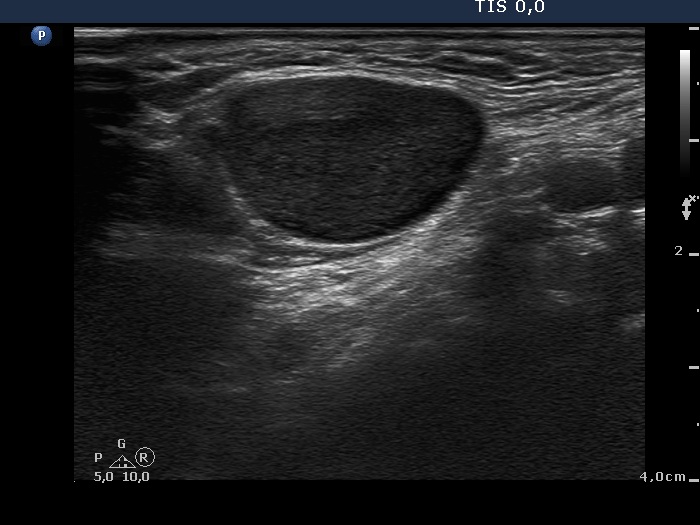

Lymph nodes in the neck - Case 1160 (ultrasonographic picture 4)

Right submandibular area, transverse scan. There is a large lymph node without regular hilum.